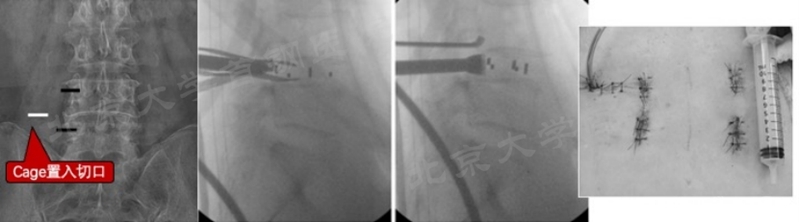

我中心也遇到部分患者因为滑脱、腰前凸过大等情况,导致左侧融合手术时置入cage角度困难,从而需要额外进行cage置入切口的情况,患者术后疼痛较其他患者明显(图12)。

图12 我中心在对严重L5-S1滑脱患者置入Cage困难时采用额外切口(图片来源我中心,引用转发需注明出处)